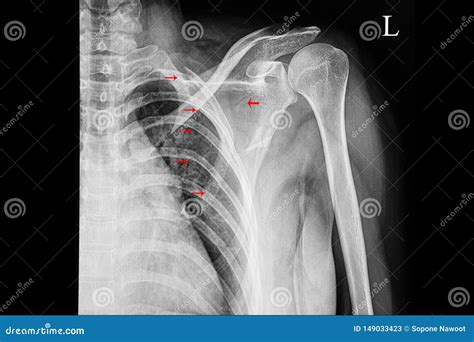

Diagnosing a Broken Shoulder Blade

Diagnosing a broken shoulder blade involves a combination of physical examination and imaging tests. The diagnostic process typically includes:

• Physical Examination: A healthcare provider will assess the shoulder for tenderness, swelling, and deformity. They will also check the range of motion and compare it to the unaffected shoulder.

• Imaging Tests: X-rays are the primary imaging tool used to diagnose a broken shoulder blade. They can show the location and extent of the fracture. In some cases, a CT scan or MRI may be ordered for a more detailed view.